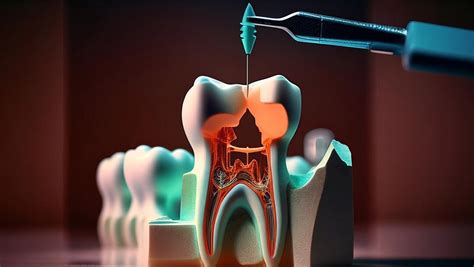

¿En qué consiste una endodoncia?

La “extracción del nervio”: la endodoncia está basada en el vaciamiento y limpieza total de los conductos donde se alberga el nervio de la pieza. Para retirar la infección por bacterias y el posible tejido necrótico/infectado existente, para dejar el conducto limpio, sin bacterias ni tejido infectado.

- Una vez que la anestesia ha hecho efecto, procedemos al aislamiento del diente mediante un dique de goma. Posteriormente, realizamos una pequeña abertura en la corona del diente para acceder a los conductos radiculares.

- Esta es la fase más importante del tratamiento de conductos. Utilizando instrumentos de alta precisión, algunos de ellos rotatorios y otros manuales, procedemos a la limpieza meticulosa del interior de cada conducto radicular. La desinfección se realiza mediante irrigación abundante con soluciones antimicrobianas especializadas que penetran en todos los recovecos del sistema de conductos.

- Una vez que los conductos están completamente limpios y desinfectados, procedemos a su sellado hermético utilizando un material biocompatible llamado gutapercha, junto con un sellador específico. Finalmente, reconstruimos la corona del diente.